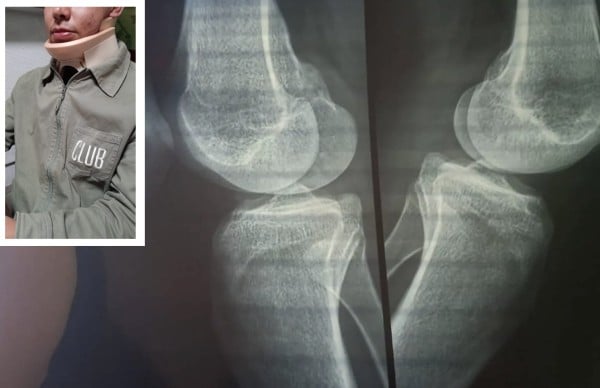

Lo anterior, luego de que el pasado martes 24 de junio, cerca de las 3:00 de la tarde, JP un menor de 17 años, fue sometido por parte de tres elementos de Policía cuando esperaba a su mamá a las afueras de la casa de su tía en la colonia mencionada.

JP fue insultado y golpeado por parte de las autoridades que llegaron presuntamente a realizar un cateo a un punto de venta de droga.

Pedimos a las autoridades que reconozcan su falta, y que la alcaldesa Alejandra Gutiérrez me apoye económicamente, porque tuve que pedir un préstamo para que revisaran a mi hijo. Le pido también tener más seguridad y que los policías que tiene dentro de la corporación sean más confiables y no abusen de su uniforme para que nosotros como ciudadanos estemos más tranquilos y no temer a quien se supone nos cuida”.

Destacó que si es necesario se debe dar de baja a esos elementos que actuaron sin un correcto protocolo, porque al parecer sin recién egresados de la Academia Metropolitana, porque los golpes que le dieron sin siquiera saber que él no sabía de lo que le estaban acusando al decirle que era distribuidor de droga y que les informara del presunto punto y a quiénes había citado en el lugar, cuando solo estaba esperando a su mamá para meterse a la casa de su tía, señaló su madre Juana.